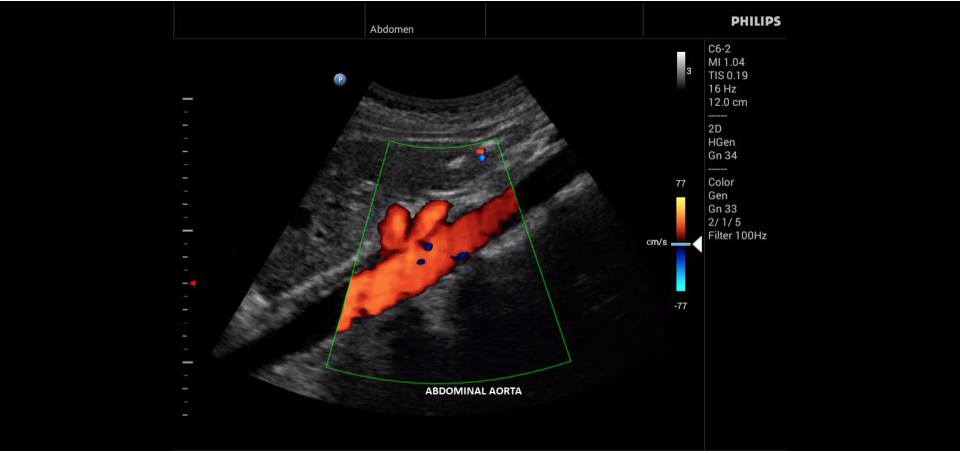

Philips InnoSight

Philips InnoSight увеличивает возможности сканирования во множестве мест оказания медицинских услуг. Благодаря данному УЗИ аппарату врачи могут не сомневаться в быстром выполнении обычных ультразвуковых сканирований во врачебном кабинете, клинике или больнице.

InnoSight позволяет перенести ультразвуковую диагностику непосредственно туда, где пациенту оказывается медицинская помощь, что повышает мобильность врачей. Этот компактный и легкий ультразвуковой аппарат позволяет чаще использовать возможности ультразвуковой диагностики и предоставляет широкий набор технологий для проведения углубленных исследований — программные пакеты для специализированного анализа, функции аннотирования и наборы готовых настроек для различных типов тканей.

Эргономичная система с высококачественными широкополосными датчиками Philips помогает повысить клиническую надежность результатов исследования и уровень оказания медицинских услуг. Аппарат можно перемещать вручную или с помощью тележки.

• Общие абдоминальные исследования;

• Исследования сосудов;

• Цветное допплеровское картирование

• Конвексный УЗИ датчик Philips С6-2